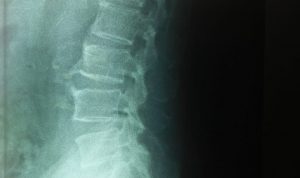

Ket//Foto: Foto Rontgen Tulang Belakang Supratyono yang mengalami Patah Tulang akibat pemukulan

ket/foto: Supratyono karyawan Apindo Sumut terlihat dipukul sampai terjatuh dan mengalami patah tulang belakang